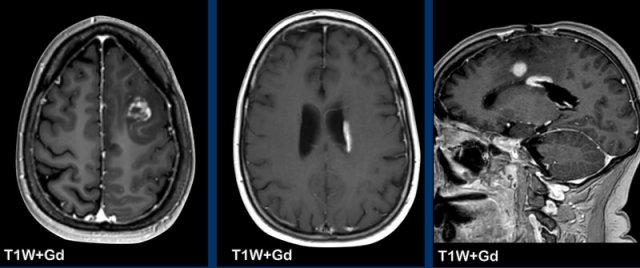

Các hình ảnh này của bệnh nhân ung thư phổi di căn. Ghi nhận hai tổn thương di căn ngấm thuốc tại bán cầu não trái.

Trên chuỗi xung T1W có tiêm thuốc tương phản từ Gadolinium, các mạch máu cũng ngấm thuốc mạnh khiến việc phát hiện các tổn thương di căn trở nên khó khăn.

Trên chuỗi xung “black blood” (xóa tín hiệu máu), tín hiệu của máu trong lòng mạch bị triệt tiêu, giúp nhận diện các tổn thương di căn ngấm thuốc dễ dàng hơn.

Ở bệnh nhân này, điểm nổi bật là một tổn thương dạng nang lớn ở thùy đỉnh phải với vòng viền ngấm thuốc không đều và một phần dày.

Có hiệu ứng khối và phù não xung quanh, không có hạn chế khuếch tán.

Có thể nghĩ đến u thần kinh đệm.

Tuy nhiên, còn có nhiều tổn thương khác ở các vị trí xa nhau.

Một trong số đó có vị trí đặc trưng tại ranh giới chất xám – chất trắng (mũi tên).

Các tổn thương này được xác định là di căn não.